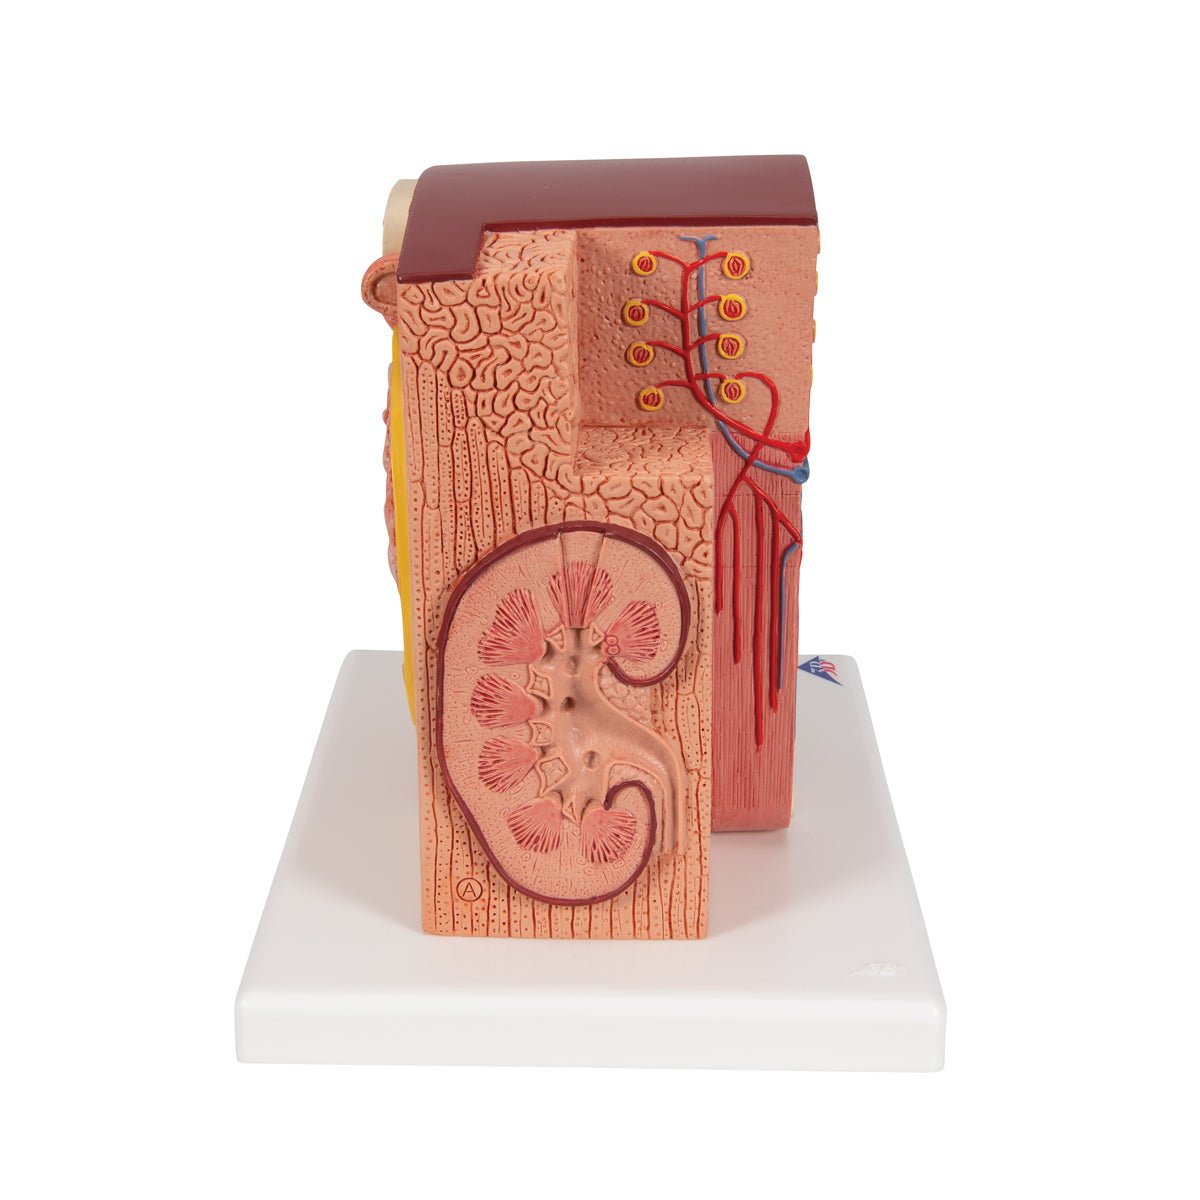

Salg af anatomiske modeller er det bærende element i eAnatomi, selvom vi også bruger mange ressourcer på at udvikle vores egne anatomiske materialer som fx plakater. Anatomiske modeller anvendes til forskellige formål og kan både vise afgrænset væv, organer samt organsystemer. Søger du en simpel model af knoglevæv eller måske en avanceret torso-model baseret på MRI teknologi, kan du finde det hele på eanatomi.com.